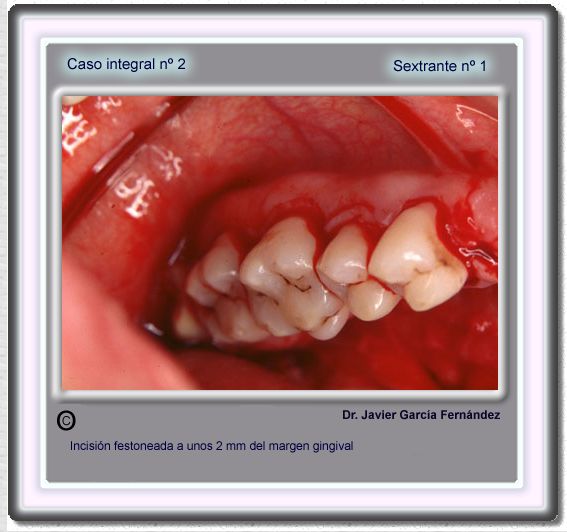

image 21